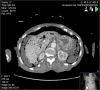

A 91-year-old female presented to the Emergency Department with a 10-day history of constipation and abdominal pain. Abdominal examination was normal and rectal examination showed faecal loading. A phosphate enema was given and the patient was admitted. Overnight, the patient's GCS dropped from 15/15 to 3/15 and an arterial blood gas showed a lactate of 8 mmol/L (1.5 on admission). Abdomen remained soft throughout. A CT scan showed a large amount of free air and free fluid within the abdomen and pelvis, highly suspicious for perforation. Hepatic portal venous gas (HPVG) was visible, with portal venous air fluid levels noted. The patient was treated palliatively and died shortly thereafter. HPVG is a recognized but rarely identified radiological sign, which is a poor prognostic indicator, with most cases subsequently proving terminal, often due to subsequent bowel necrosis.